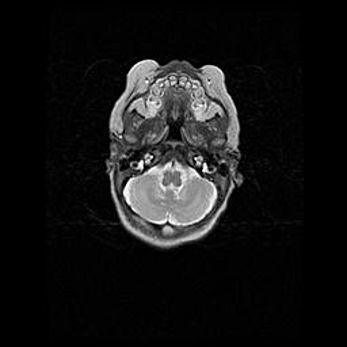

Подострая гематома правой гемисферы мозжечка.

Наружная гидроцефалия.

Возраст: 15 дней

Вес: 3100 г

Пол: женский

Окружность головы: 37 см

Срок гестации: 35-36 недель

При открытой наружной форме гидроцефалии у новорожденных расширяются и переполняются субарахноидные пространства.

Кровоизлияния в мозжечок имеют две клинико-анатомические формы: полушарные гематомы и кровоизлияния в червь.

К появлению этой патологии может привести: повреждения головного мозга, возникающие в результате асфиксии и гипоксии плода при беременности, или травмы во время родов. Редко гематома мозжечка может быть результатом первичной коагулопатии и сосудистой мальформации, диссеминированном внутрисосудистом свертывании, изоиммунной тромбоцитопении.